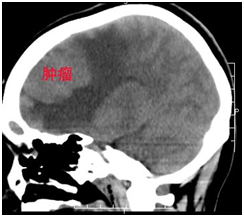

梁女士,44岁,某公司中层管理者,工作非常繁忙,正当她准备在工作上大展拳脚的时候,突如其来的头痛让她烦躁不安。由于每天加班到深夜,回家后倒头就睡,让她无暇关注自己的身体。因为头痛在休息时可以得到缓解,梁女士就没有在意,忙完生意后才抽出时间到医院进行身体检查。这一查不打紧,检查结果着实把梁女士吓丢了魂。原来梁女士的脑子里长了一个大瘤子,头痛就是因为瘤子压迫脑组织引起的。2015年10月开始出现发作性头痛,持续2月,为求进一步治疗入住我院,入院诊断:矢状窦旁脑膜瘤。体查未发现明显阳性体征,排除手术禁忌症,予以手术切除肿瘤组织,头痛症状缓解,术后病理检查提示:混合型脑膜瘤(I型)。